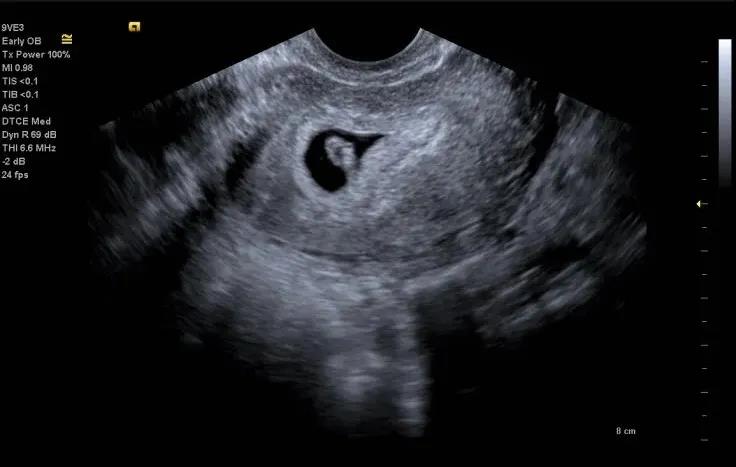

怀孕6-8周 确定宫内孕

怀孕后第一次超声检查,首先要确定宫内妊娠,建议在6-8周左右进行,如果有腹痛、阴道流血等症状应及时到医院检查,确认是否为宫外孕。目前临床上应用的超声参数都在安全剂量范围内,早孕期超声检查是安全的,阴式超声检查也是安全的,对于怀疑宫外孕者更应该做阴式超声检查明确诊断。